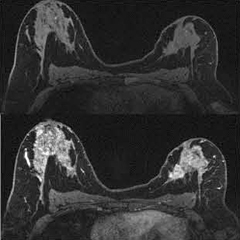

●診断ワークフロー

近年の高磁場化,高画質化に伴い,検査後の大量なデータを扱った診断において,ワークフローを改善することが装置メーカーの責務となっています。シーメンスは,画像解析処理システムである“syngo.via”に搭載されている“syngo BreVis”を用いることで,大量の検査データから自動的に診断に必要な解析結果,計測結果を表示し,今までの煩雑な解析手順を,簡便で定量的な自動化へと変化させました(図3)。

またsyngo.viaには,米国放射線専門医会(ACR)により提唱されたBI-RADS(Breast Imaging Reporting and Data System)-MRIに準拠した診断レポーティングシステムである“Breast Care Reading”を搭載し,統一した読影方法,所見用語,カテゴリー分類を簡便に選択し,診療科への提供が可能となります(図4)。

図3 syngo BreVis

図4 Breast Care Reading